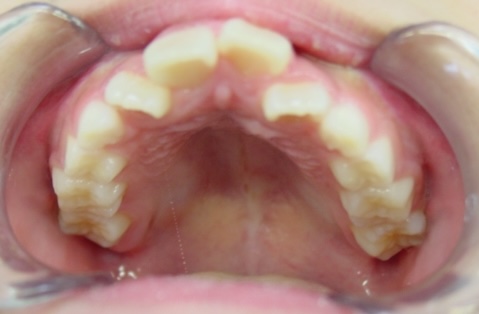

矯正後

| 通院目的 | 永久歯を抜かずに歯並びを治したい。 |

| 処置内容 | バイトブロック・プレート拡大処置・ディスタライザー・インビザライン・オーソテイン・マルチブラケット装置・プリフィニッシャー |

| デメリット・院長コメント | 永久歯を抜かない治療のデメリットは、治療期間が長いことです。 ただし、その後の人生の長さを考えると、健全な小臼歯を2本または4本抜歯の矯正治療よりも、はるかにメリットがあるといえます。 また、アーチが小さくならないので、舌が後ろに押し込まれないためいびき防止につながり睡眠の質の向上にもつながります。 |